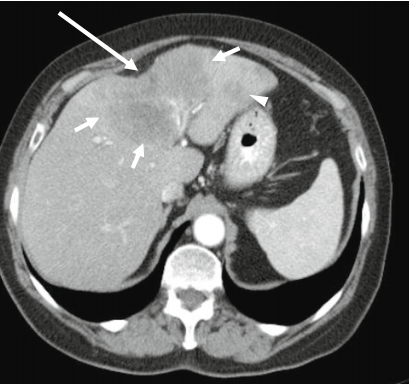

肝包膜皱缩除了胆管细胞癌还有这几种情况